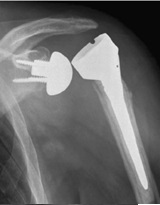

反轉式全人工肩關節置換術,幾經多次修改,術後的臨床表現的確比傳統式肩全人工關節 (圖7)

好很多,術後關節的疼痛、 僵硬、 活動度都大有改善,術後併發症也大大減少。

但反轉式全人工肩關節卻存在 肩盂假體 緊貼肩胛頸部的下緣,造成撞擊、磨損、蝕骨,甚或鬆脫的弊病。 (圖8-1, 2, 3)

![]() |

| 圖 7 傳統式肩人工關節 |